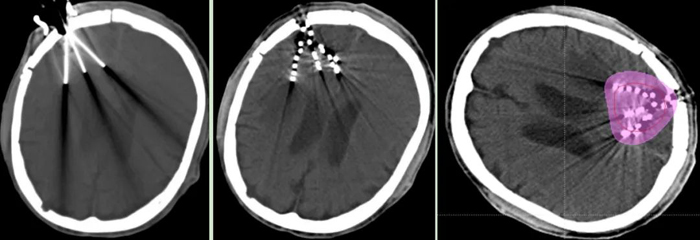

近日,我院腫瘤一科成功為一名腦膠質母細胞瘤術后放療后復發患者,實施“CT引導腦部腫瘤125I放射性粒子植入術”。

經腫瘤科、神經外科、影像科等科室多學科討論,認為患者無再次手術及放療指征,決定行“CT引導125I放射性粒子植入術”。經周密術前準備,在神經外科吳超副主任醫師協作下,張開賢主任帶領粒子治療團隊歷經2個小時,在CT精準引導下,成功完成了125I放射性粒子植入術,現恢復良好。術后劑量驗證,達到術前計劃要求。